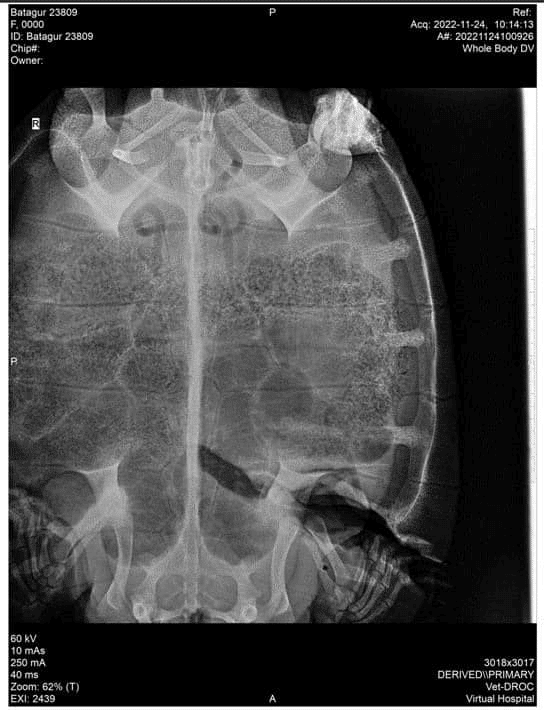

ក្រោយពីបានស្គាល់ថាអណ្តើកនោះជាប្រភេទអណ្តើកហ្លួងដែលត្រូវការពារ អ្នកនេសាទនោះបានយកមកប្រគល់ជូនក្រុមការងារអង្គការ WCS ប្រចាំស្រុកស្រែអំបិល ដើម្បីពិនិត្យព្យាបាល។ អណ្តើកនោះមានទម្ងន់១៤,៩គីឡូក្រាម បានរងរបួសដាច់ស្នូកខ្នងផ្នែកខាងឆ្វេងធ្លាយពីលើដល់ក្រោម ទំនងជាត្រូវរបួសដោយសារស្លាបចក្ររបស់សាឡង់ ឬកប៉ាល់ដឹកខ្សាច់ ឬទំនិញធំៗ ដែលចរាចរតាមផ្លូវទឹកផ្នែកខាងក្រោមនៃប្រព័ន្ធព្រែកស្រែអំបិលជាប់នឹងឆកសមុទ្រនៃស្រុកស្រែអំបិល។

យោងតាមទិន្នន័យនៅក្នុងបន្ទះឈីប (Chip) ដែលបង្កប់នៅក្នុងជើងក្រោយរបស់អណ្តើកនោះ ក្រុមការងារអង្គការ WCS អាចស្គាល់អត្តសញ្ញាណច្បាស់ថា អណ្តើកនោះត្រូវបានលែងចូលក្នុងប្រព័ន្ធព្រែកស្រែអំបិលកាលពីចុងខែវិច្ឆិកា ឆ្នាំ២០២១ ក្រោមគម្រោងអភិរក្សអណ្តើកហ្លួង ដែលអនុវត្តដោយអង្គការ WCS សហការជាមួយរដ្ឋបាលជលផល។ ដោយពិនិត្យឃើញស្នាមរបួសមានសភាពធ្ងន់ធ្ងរ ក្រុមការងារអភិរក្សអណ្តើកហ្លួងនៃអង្គការ WCS សហការជាមួយរដ្ឋបាលជលផល និងឆ្លងតាមការពិគ្រោះយោបល់ជាមួយអ្នកជំនាញនៅមជ្ឈមណ្ឌលអង្គរសម្រាប់ការអភិរក្សជីវៈចម្រុះ (ACCB) បានបញ្ជូនអណ្ដើកនេះ ទៅកាន់មជ្ឈមណ្ឌល ACCB នៅក្នុងខេត្តសៀមរាប ដើម្បីពិនិត្យនិងព្យាបាល។